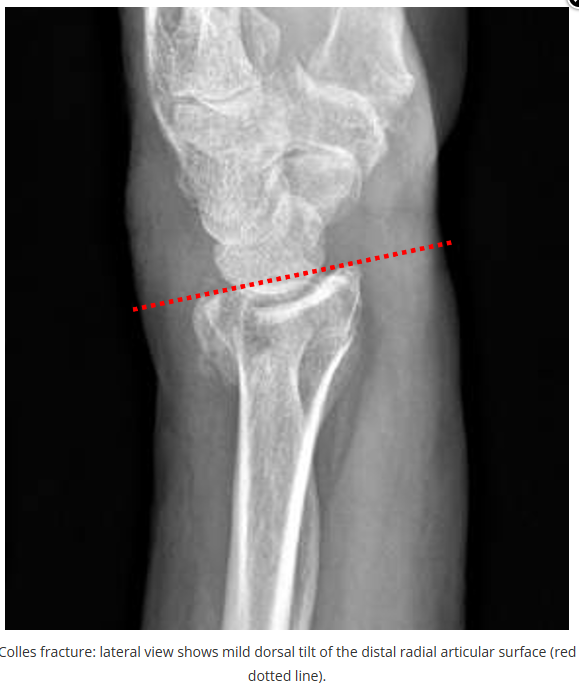

今天是腕部与手的X线片。所有X线片都

带有标注和说明

,可以选择长按图片,

自动翻译相关说明